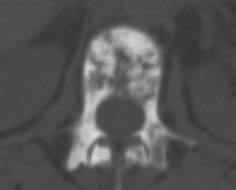

• a bone scan or CT are more sensitive than plain Xrays (see right hip met and see rib mets).Advanced spine mets can lead to spinal cord syndrome go here.

• MRI is also more sensitive than plain Xrays. A woman had severe pain in her arm , the Xray was read as normal but the MRI was markedly abnormal (see here) she later developed a pathologic fracture see here. (other cases:  see spine , spine, here and MRI) see MRI showing a pathologic fracture from lymphoma here. The specific MRI rechnique will influence the way bone mets appear (go here)